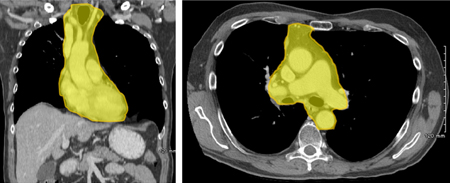

纵隔,是胸廓内的一个解剖部位,指两侧肺脏层胸膜间的胸内空间。如果用文字描述纵隔的边界:即上界为胸廓入口,下界为横膈,前为胸骨、后为脊柱,两侧为脏层胸膜如图一。

图一,胸部CT上看,黄色部分为纵隔的区域

纵隔内容物包括心脏、大血管、胸腺、淋巴组织和神经,以及气管和食管。